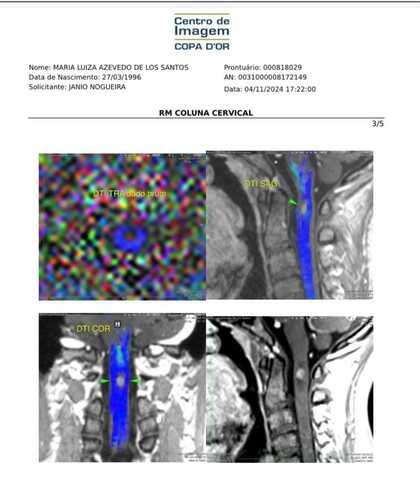

Hoje escrevo com o coração apertado para compartilhar um momento muito difícil que nossa família está vivendo. Minha filha, Maria Luiza, recebeu recentemente um diagnóstico que mudou completamente a vida dela e todos os planos. Ela tem um tumor raríssimo na medula espinhal, que somente será confirmado após uma biópsia, mas os médicos acreditam que seja um ependimoma. Em outras palavras, estamos lidando com um câncer.

Depois de uma longa jornada de exames e consultas, ficou claro que a única solução é uma cirurgia para remover o tumor. No entanto, este procedimento é extremamente delicado. O tumor está em uma área crítica da medula espinhal, e há riscos seríssimos caso a cirurgia não seja conduzida por profissionais altamente capacitados. Esses riscos incluem tetraplegia, perda permanente de funções motoras, incapacidade respiratória e até mesmo consequências mais graves. Alguns médicos até se recusaram a realizar a operação devido à complexidade.

Felizmente, encontramos uma equipe médica excelente, que está otimista quanto à possibilidade de cura e de uma recuperação bem-sucedida. Porém, o tempo é um fator crucial. O tumor continua crescendo e já está causando sintomas que pioram a cada dia. Se não agirmos rapidamente, o risco de sequelas permanentes aumenta significativamente.